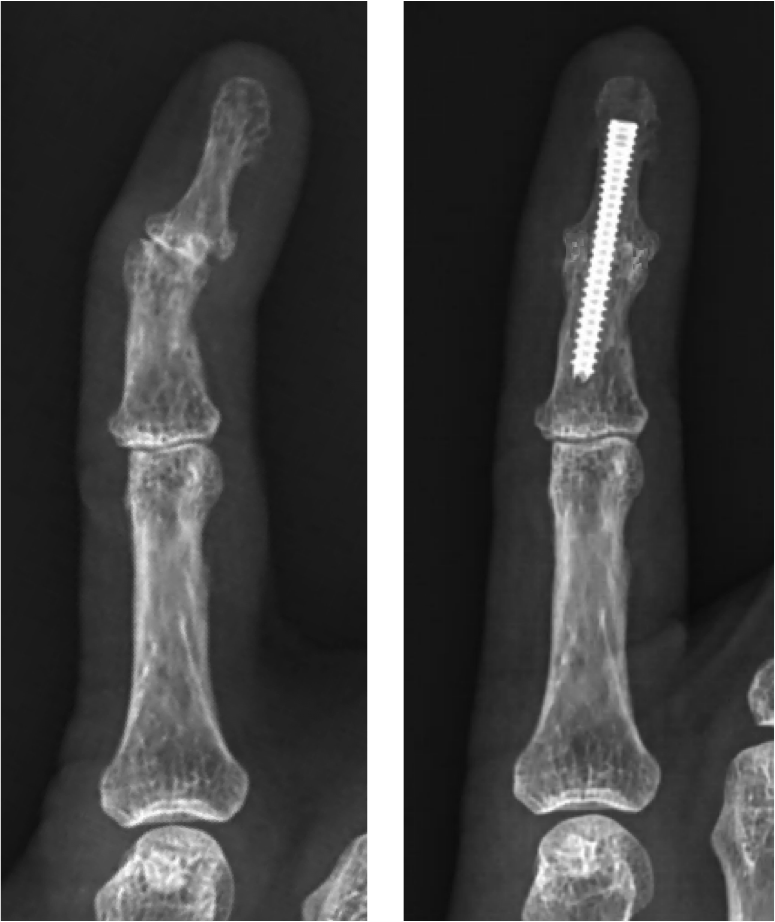

Finger Distal Interphalangeal Joint Fusion Surgery Performed by Dr Arthritis Finger Operation The two main surgical options for hand arthritis are fusion (arthrodesis) and total knuckle replacement (arthroplasty). one reason is that finger surgery has a high complication and failure rate. It can also sacrifice mobility for pain relief. the most common surgery that's done for treatment of finger arthritis is a finger joint fusion. Surgery to treat interphalangeal joint. Arthritis Finger Operation.

Arthritis Distal Interphalangeal Joint Arthroplasty with reversed Arthritis Finger Operation It can also sacrifice mobility for pain relief. 3 min read. 10k+ visitors in the past month surgery for arthritis in fingers. Surgery to treat interphalangeal joint arthritis is typically an outpatient procedure that lasts about an hour. Review this list of arthritis surgery options. the most common surgery that's done for treatment of finger arthritis is. Arthritis Finger Operation.

Finger Joint Fusion Surgery EsHealthTips Arthritis Finger Operation Review this list of arthritis surgery options. one reason is that finger surgery has a high complication and failure rate. 3 min read. The two main surgical options for hand arthritis are fusion (arthrodesis) and total knuckle replacement (arthroplasty). the base of your thumb, your knuckles, second joint and top joint of your fingers are common sites. Arthritis Finger Operation.